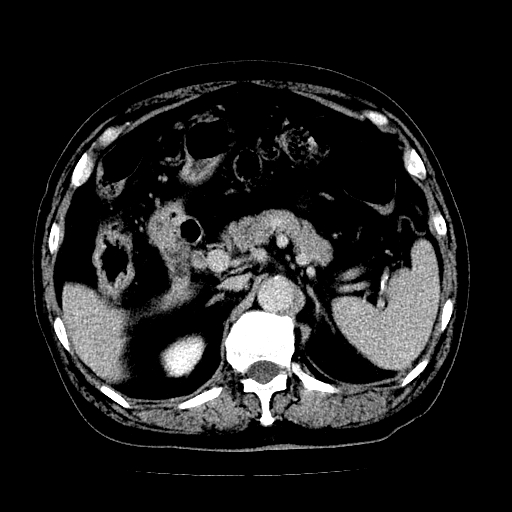

男,71岁,皮肤黄染四天。

肝内外胆管及胆总管上段扩张,考虑为梗阻所致,建议mrcp检查。

考虑胆总管癌并肝内外胆管扩张。

支持考虑胆总管癌并肝内外胆管扩张。 局部应薄扫。心包钙化。

胰腺上端胆总管内见软组织影,强化不明显,结合临床,还是考虑低位梗阻性黄疸,胆总管癌可能性大